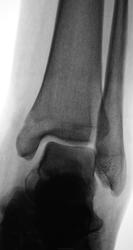

Сказал лаборанту сделать косую проекцию

Только после последнего снимка и на стандартных проекциях, очень внимательно приглядевшись, увидел линию перелома...

Линия перелома

Снимаю шляпу! Я думала, что этот контур закрывшаяся зона роста.